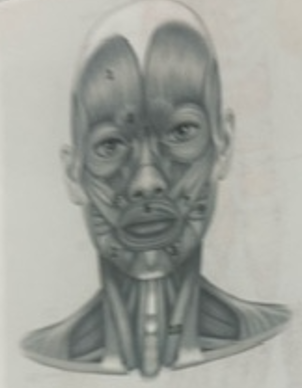

What muscle is 1?

Frontalis

What muscle is 2?

Depressor anguli oris

What muscle is 3?

Depressor labili inferioris

What muscle is 4?

Corrugator supercili

What muscle is 5?

Orbicularis oris

What muscle is 6?

Zygomaticus minor

What muscle is 7?

Zygomaticus major

What muscle is 9?

Buccinator

What muscle is 10?

Sternocleidmastoid

What muscle is 11?

Temporalis

What muscle is 12?

Masseter

What muscle is 13?

Risorius